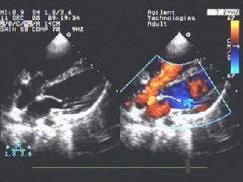

彩色都卜勒血流顯像

以彩色的亮度表現紅藍相混的雜色。1980年代發展的新技術將血流顯色,重疊於黑白的二維或M型心動圖上,可更清楚地顯示結構異常和血液動力學異常的關係,這即是彩色都卜勒血流顯像。用自相關技術和彩色編碼處理,一般將血流朝向探頭的顯示為紅色,背向探頭的血流顯示為藍色,以色彩的亮度表示血流速度,出現渦流時,由於血流方向不同,出現紅藍相混的雜色。這樣便可以觀測心臟或大血管內血流的方向、途徑,血流性質,有無異常血流束等,可以診斷瓣膜有無狹窄、返流,有無異常的分流等(彩圖)。本法主要優點為:①快速篩選正常和異常血流,尤其是檢測異常的分流和返流;②區別發生在相同心動周期,來自不同部位而方向相似的血流,如聯合瓣膜病變的和多發性分流;③通過射流方位的顯示,指導連續波或脈衝都卜勒探測,提高定量分析心排血量及壓差的準確性;④對返流和分流病變,可提供簡便的半定量診斷方法。不足之處是二維結構顯象的質量因幀數減少而降低。